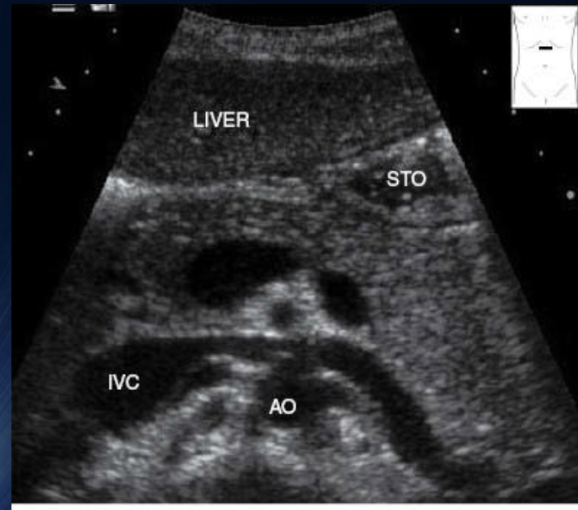

What is this + Label

Trv Proximal Aorta (SMA lvl)